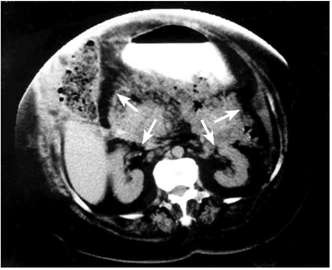

בבדיקה תימצא רגישות ניכרת בבטן, אולם בלא התאמה לעוצמת הכאב עליו מספר החולה, לרוב בלא גירוי צפקי. במקצת החולים הלוקים בהתקף חריף ובנמק של הלבלב או בסיבוכים, יימצא גם גירוי צפקי. גוש בבטן עליונה ניתן למצוא ב-20%. שינוי צבע העור (דיסקולוריזציה) סביב הטבור (הסימן על-שם Cullen), או באזור המותניים (הסימן על-שם Grey turner), היא עדות לדימום בחלק האחור-צפקי (תמונה 1.9).

- טומוגרפיה ממוחשבת היא בדיקת הבחירה לאבחון דלקת הלבלב. יש לבצע טומוגרפיה ממוחשבת בחולי דלקת לבלב חריפה שבהם התהליך אינו משתפר במשך יומיים-שלושה, ואם מופיעים סיבוכים או מתקיימים יותר משלושה קריטריונים על-שם Ranson. הממצאים יכולים להיות:

- לבלב בצקתי (תצלום 1.9);

הזילוח של רקמת הלבלב מתבטא בעוצמת ההאדרה לאחר הזרקת חומר ניגוד והתפלגותו בלבלב חשובה. ככל שההאדרה קטנה יותר, כך הנמק בלבלב רב יותר (תצלום 2.9). חולים שבהם נמצא בטומוגרפיה ממוחשבת נמק של יותר מ-50% מהלבלב יפתחו יותר זיהומים מחולים שבהם נמצא נמק קטן יותר, ולכן יזדקקו יותר לניתוחים. יש המבצעים בהנחיית טומוגרפיה ממוחשבת דיקור של הלבלב ושואבים ממנו חומר לתרבית. תרבית חיובית של הנמק מחייבת ניתוח.